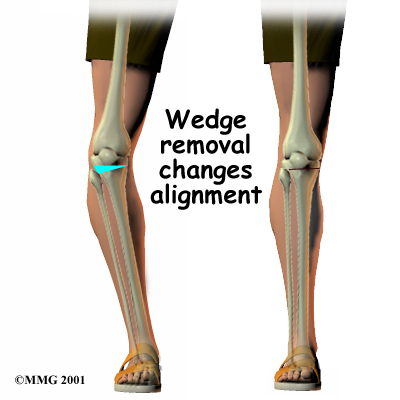

There are two methods to realign the knee joint. One involves taking out a wedge of bone; the other involves adding a wedge of bone. Any operation for cutting through a bone is called an osteotomy. In a closing wedge osteotomy, the surgeon cuts though the tibia on the lateral side, removes a wedge of bone, and pins the open edges together. In an opening wedge osteotomy, the surgeon cuts though the tibia on the medial side and opens a wedge, adding a bit of bone graft to hold the wedge open.

There are two methods to realign the knee joint. One involves taking out a wedge of bone; the other involves adding a wedge of bone. Any operation for cutting through a bone is called an osteotomy. In a closing wedge osteotomy, the surgeon cuts though the tibia on the lateral side, removes a wedge of bone, and pins the open edges together. In an opening wedge osteotomy, the surgeon cuts though the tibia on the medial side and opens a wedge, adding a bit of bone graft to hold the wedge open.

Closing Wedge Osteotomy

In the , an incision is made in the lateral side of the knee to allow the surgeon to see the upper end of the tibia. Care is taken to protect the nerves and blood vessels that travel across the knee joint.

Once the tibia bone is exposed, two cuts are made through the upper tibia in the shape of a wedge. The surgeon uses either X-rays or a fluoroscope, a special kind of X-ray machine that casts images on a fluorescent screen, to make sure the wedge is the right size and is placed correctly.

The surgeon takes out the wedge, and the two sides of the tibia are brought closer together and held in position with a metal plate or pins. This and helps straighten the alignment of the knee. After fixing the two edges of bone with a plate or pins, the surgeon stitches the skin together, and the leg is placed in a padded splint to protect the knee joint.

There are two methods to realign the knee joint. One involves taking out a wedge of bone; the other involves adding a wedge of bone. Any operation for cutting through a bone is called an osteotomy. In a closing wedge osteotomy, the surgeon cuts though the tibia on the lateral side, removes a wedge of bone, and pins the open edges together. In an opening wedge osteotomy, the surgeon cuts though the tibia on the medial side and opens a wedge, adding a bit of bone graft to hold the wedge open.

There are two methods to realign the knee joint. One involves taking out a wedge of bone; the other involves adding a wedge of bone. Any operation for cutting through a bone is called an osteotomy. In a closing wedge osteotomy, the surgeon cuts though the tibia on the lateral side, removes a wedge of bone, and pins the open edges together. In an opening wedge osteotomy, the surgeon cuts though the tibia on the medial side and opens a wedge, adding a bit of bone graft to hold the wedge open.